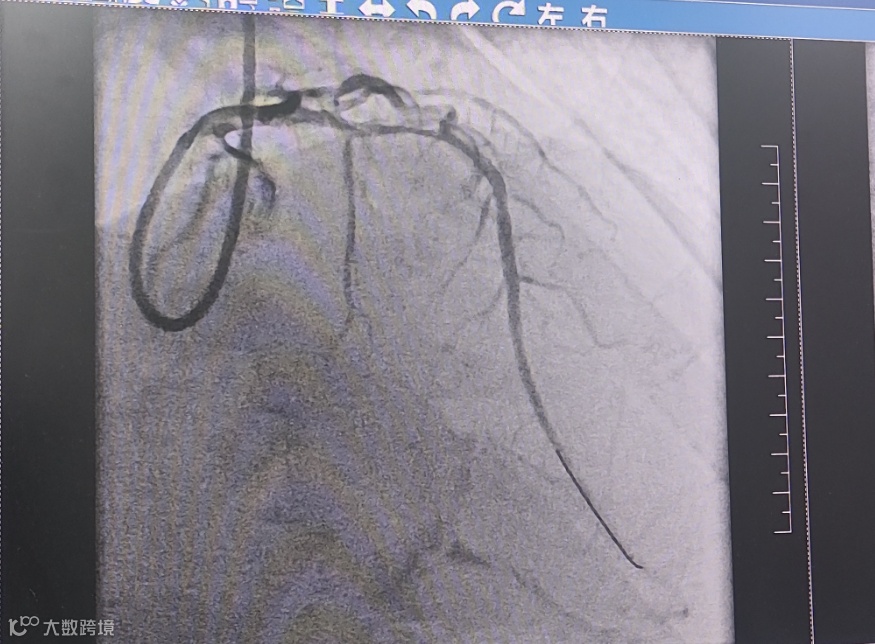

(球囊扩张与溶栓后血管通畅)